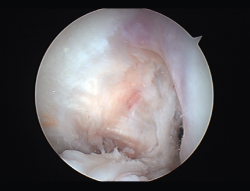

Rigidez

Una de las complicaciones más temidas, producida por un aumento del tejido fibroso, ya sea por la propia lesión (primaria) o secundaria a diferentes motivos (error técnico en la cirugía, síndrome del cíclope, inmovilización prolongada o la participación insuficiente en un programa de rehabilitación, infección, síndrome del dolor regional complejo, hematomas o sinovitis) (Figuras 7 y 8). Esta puede variar desde una ligera limitación del rango de movilidad hasta una severa artrofibrosis(21).

Figura 7. Adherencias intraarticulares.